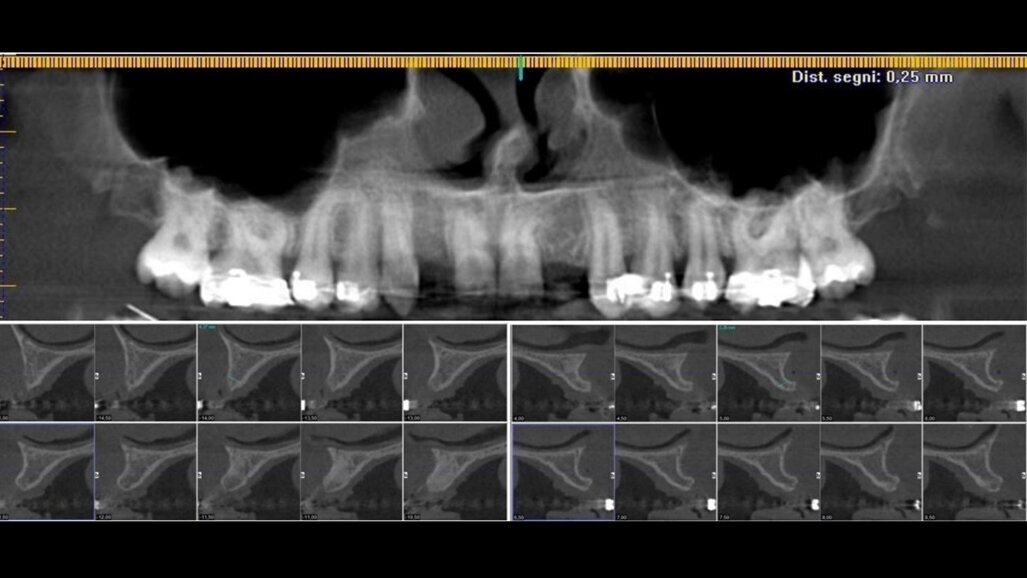

Si è proceduto ad acquisire una scansione CBCT dell’arcata nonché un’impronta digitale, utilizzando un repere su bite personalizzato per permettere il successivo matching delle immagini. Le sezioni CBCT evidenziavano creste di dimensioni ridotte (Fig. 2a) e un’accentuata concavità vestibolare in posizione 22 (Fig. 2b). Il progetto implantare ha previsto l’inserimento di due impianti B1ONE HIGH di dimensioni 3,2 x 12 mm in posizione 12 e 2,7 x 12 mm in posizione 22 (Fig. 3a). Gli impianti selezionati hanno piattaforma SMALL (Ø di 3 mm) e sono caratterizzati da una morfologia di spira (tipo HIGH) realizzata in conformità alle caratteristiche dell’osso24. Contestualmente all’inserimento implantare, la misurazione dell’integrale della curva torque-profondità ha dato conferma di stabilità dell’impianto25, 26. La progettazione implantare è stata quindi condivisa con un laboratorio specializzato (IDI Makers, IDI Evolution) per la realizzazione della corrispondente mascherina chirurgica per chirurgia guidata, con allestimento di piccoli lembi a spessore totale (Fig. 3b).

Fig. 2_Valutazione della disponibilità di spazio mesio-distale e di spessore dell’osso vestibolare; a) visione occlusale in corrispondenza degli elementi 12 e 22; b) immagine panoramica successiva a CBCT con sezione dell’osso vestibolare.